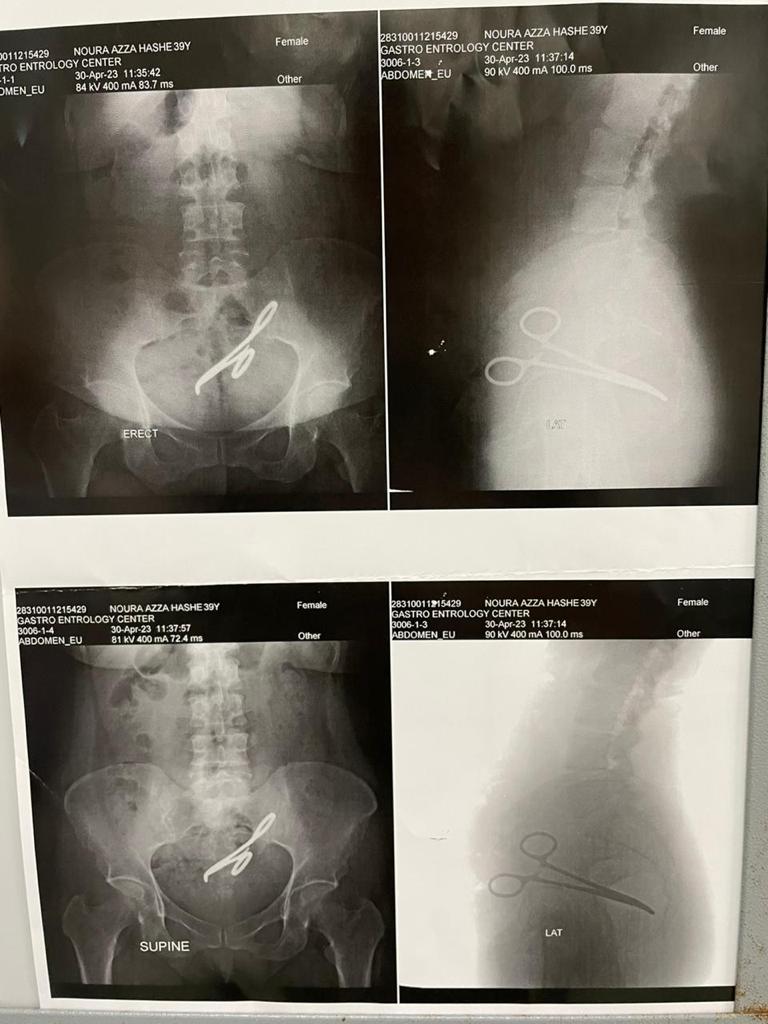

وذبك في واقعة فريدة من نوعها حيث تم اكتشاف آلة جراحية «جفت شرياني» بداخل تجويف البطن لسيدة أجري لها عملة جراحية سنة 2017 «ولادة قيصرية».

وصرح الدكتور أمجد فؤاد رئيس اقسام الجراحة، أن هذه السيدة حضرت فى العيادة الخارجية بمركز جراحة الجهاز الهضمي بجامعة المنصورة وتم مناظرة الحالة ووجد أن بها شئ غريب وغير معتاد لذا أجرى لها على الفور الاشعات والمناظير والفحوصات اللازمه وعندها تم اكتشاف جسم معندي موجود بمنطقة الحوض لهذه السيدة.

وفي بداية هذا العام 2023 بدات هذه السيدة تعاني من آلام بالبطن والحوض وتكررت عليها هذه الآلام وازدادت حدتها وبدأ ظهور أعراض أخرى عبارة تعاني منن وجود إفرازات شبيهة بالبراز منطقة المهبل لذا فقد أسرعت على الاستشارة الطبية المكثفة التي أثبت من خلالها وجود جسم معندي فى منطقه الحوض شبيه بآلة جراحية.

وبعد التحضير المكثف والدقيق تم استكشاف الحالة فى مركز جراحة الجهاز الهضمى جامعة المنصورة، وجد خلالها آلة طبية جراحية بمنطقة الحوض عبارة عن جفت شرياني أصاب القولون والمستقيم والمثانة وعنهم الرحم بالالتهابات والالتصاقات الشديدة التي أسفرت عن حدوث ناسور بين المستقيم والمهبل

وفي جراحة صعبة ودقيقة ومعقد تم استخراج الجفت الشرياني وتم استئصال الأجزاء المصابة وذلك في خلال 5 ساعات كامله.